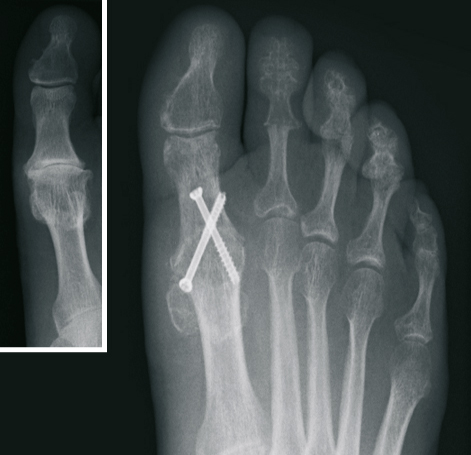

Der Hallux valgus (Ballenzehe)

Von einer operativen Korrektur ohne Vorhandensein von Schmerzen, d. h. aus rein kosmetischer Sicht, ist abzuraten. Bei Auftreten von Schmerzen im Bereich der Großzehe ist die operative Vorgehensweise jedoch die einzig dauerhafte therapeutische Möglichkeit.

Nach ausführlicher Untersuchung, Betrachtung der individuellen Erfordernisse, sowie Analyse der Röntgenbilder wird die Behandlung festgelegt. Hierbei kommen verschiedene international anerkannte Operationsverfahren zur Anwendung. Wir verwenden dabei modernste Platten und Schrauben aus Titan.

In Abhängigkeit vom Ausmaß der Operation bzw. dem zur Anwendung kommenden Verfahren, haben wir die Möglichkeit sowohl eine ambulante, als auch eine stationäre Behandlung durchzuführen.